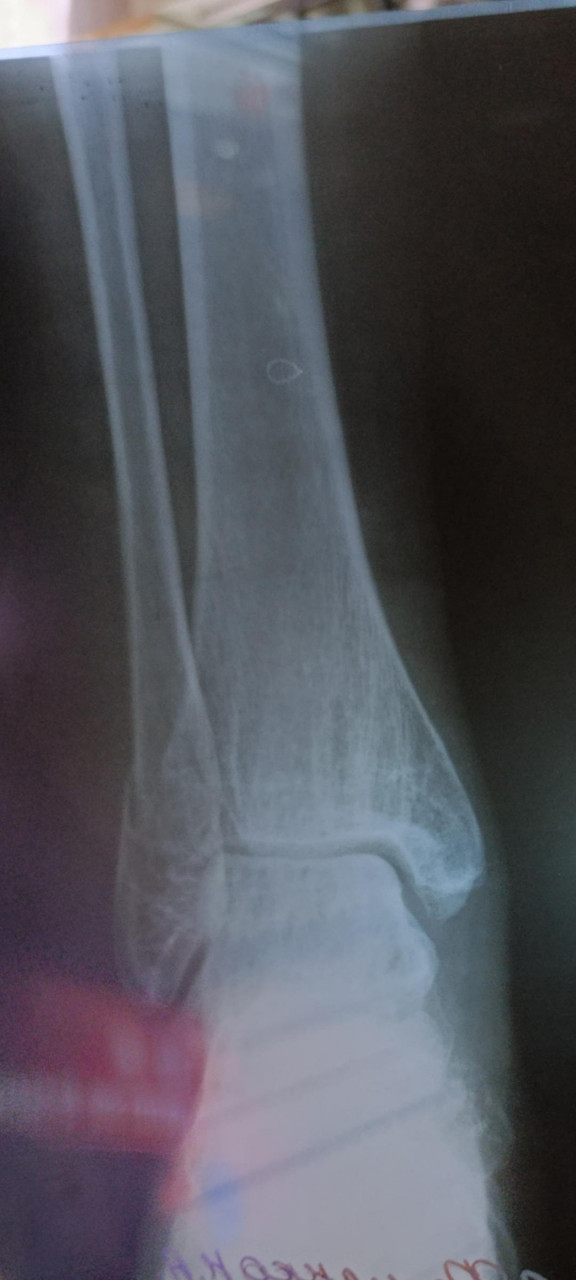

Здравствуйте. Добавила более ясное фото.. Такой снимок на рентгене. У меня перелом, а вот чего именно врач не сказал. Кости или самой лодыжки? Наложили гипс, но он очень стал давить. Пришла на прием к травматологу и его сняли с болью, просто ужас. И

отправили домой, вообще без ничего. Сказали купите ортез и носите. Оденете дома. Я на костылях пропрыгала почти 2 суток в эластичном бинте. Скажите пожалуйста, снятие гипса не может повлечь за собой дальнейшее смещение и перелом именно какой части у меня? Спасибо

Здравствуйте. На снимках виден перелом в области лодыжки, предположительно дистального отдела малоберцовой кости. Снимок с красным пятном не информативен для оценки. Снятие гипса при нестабильных переломах может привести к смещению, поэтому ортез нужно носить постоянно, а контрольный рентген обязателен. Рекомендую как можно скорее повторно обратиться к травматологу для уточнения стабильности перелома и правильной фиксации.